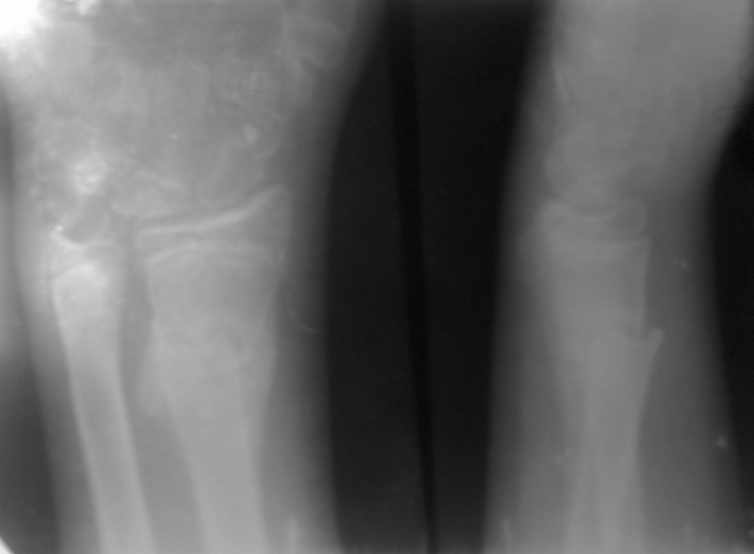

больной 13 лет.

травма полтора месяца тому.

Был сделан рентген, после чего закрытая репозиция под общим наркозом и наложена гипсовая повязка до средней 3 плеча.

пришли теперь спустя полтора месяца. На контроле, сделанном сегодня - такая ситуация.

ртг сделано без гипса. визуальных деформаций не видно. Припухлости нету. Жалоб малейших нету.

Что вы скажете про данный случай. Рентгенологически мне это очень не нравится.